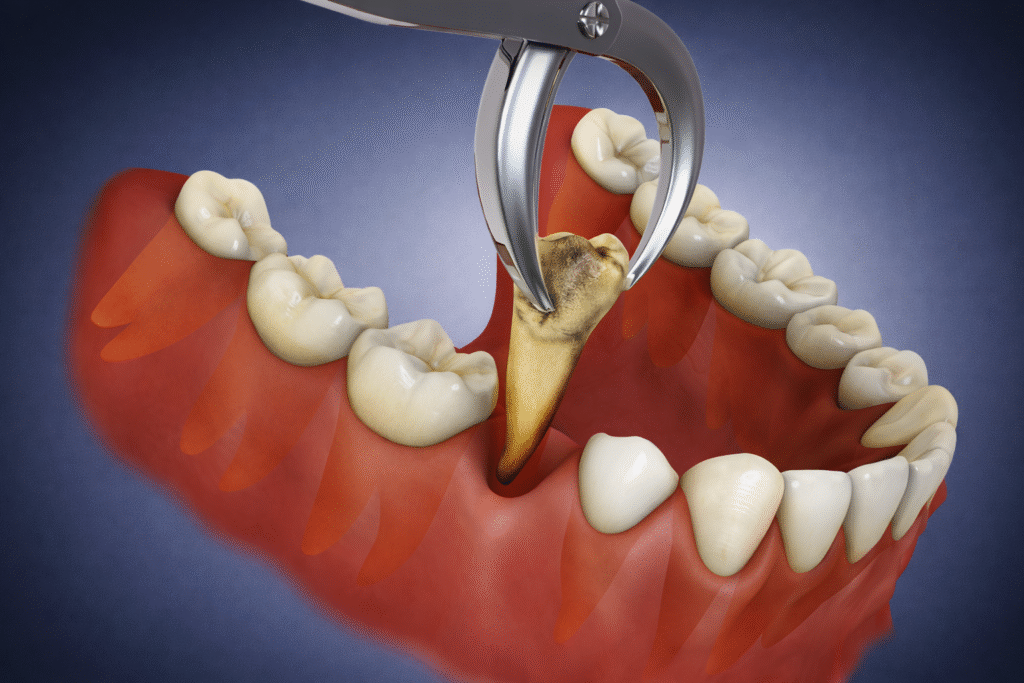

Teeth Extraction

At Our Dental Clinic in Pandalam and Pathanamthitta, The maxillofacial surgeons of Share A Smile performs teeth extractions with precision and care to ensure utmost patient comfort. Additionally, Our maxillofacial surgeon performs the extraction procedure, no matter how complex. We understand it is the most common procedure that gives nightmares to patients and dentists alike. Moreover, we strive to make it as simple and comfortable as possible. You can trust our dental clinic as you trust yourself!

Impacted Teeth Removal

The condition when a tooth or multiple teeth fail to erupt into the oral cavity even after the average eruption period is called impaction and needs surgical removal (mostly under local anesthesia). Additionally, the most common tooth/teeth that get impacted are wisdom teeth, followed by canine teeth. At Share A Smile, we will explain the procedure so you may know what to expect and make you as comfortable as possible.

What is the process for wisdom teeth extraction?

Wisdom teeth extraction is a standard oral surgery procedure. The surgeon will typically evaluate your teeth using X-rays, discuss the procedure and anesthesia options, and schedule the surgery.The surgeon removes impacted or problematic wisdom teeth during the procedure and provides you with post-operative care instructions.